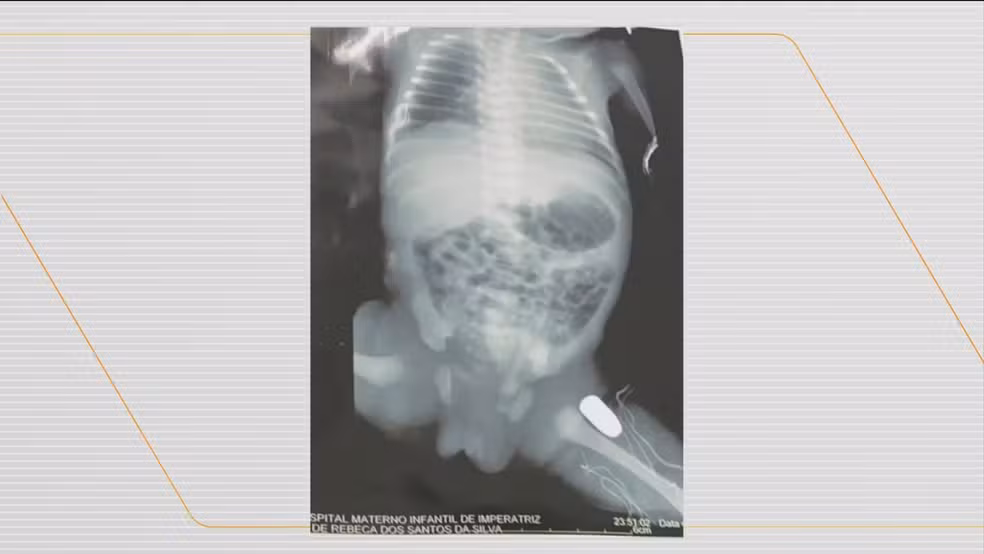

Bebê é baleado dentro da barriga da própria mãe no Maranhão